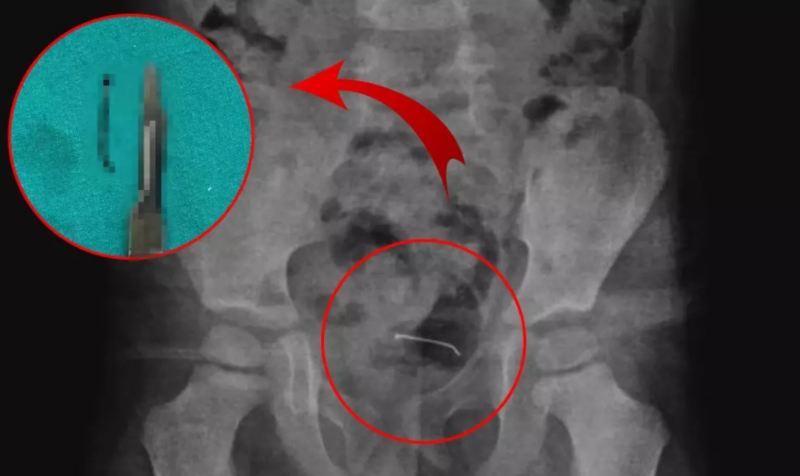

Sonxeber.az türk mediyasına istinadən xəbər verir ki, qarın ağrısından şikayət edən uşağın rentgenoqrafiyasında sidik kisəsinin divarında metal əşya aşkar edilib.

Təxminən 3 santimetr uzunluğunda olan və uzun müddət bədəndə qalan sancağın sidik kisəsinin divarına yapışdığı müəyyən edilib.

Ailənin məlumatlandırılmasının ardından Uşaq Cərrahiyyəsi Mütəxəssisi Op. Dr Tahsin Onat Kamçı tərəfindən həyata keçirilən əməliyyat nəticəsində uşağın udduğu sancaq onun bədənindən çıxarılıb.